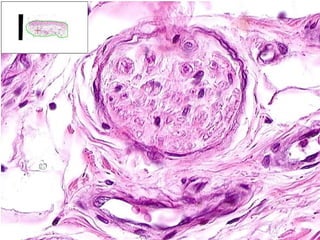

• #47 Schwannoma But really, could this be ANY soft tissue tumor?

• #48 Antoni A: Palisading, “Verocay” bodies Antoni B: Edema, “myxoid”